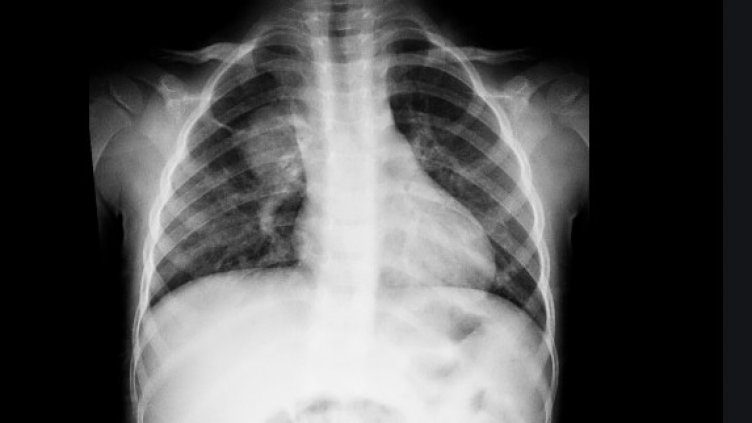

“Определено зачестяват случаите. Повече са и малките деца, кърмачетата до 1 г. и новородените, тъй като много от родителите им не са преболедували и ваксинирани. Сега се заразяват много от младите хора и тези родители го предават и на децата си. Най-малките ни пациенти обикновено са от 20-дневна възраст нагоре, когато вече са имали и малко повече контакти, това допринася да се заразят”, категорична е д-р Масларска. Тя очаква случаите да скочат с тръгването на децата на училище и детска градина. При сегашната вълна децата боледуват по-тежко. Новородените например често вдигат температура и я поддържат известно време, което не е характерно за тях попринцип. Наред с останалите типични за възрастните симптоми - липса на апетит, повръщане, диария, сега децата правят и почесто пневмонии, което не беше характерно в предишните вълни, отчита лекарката.